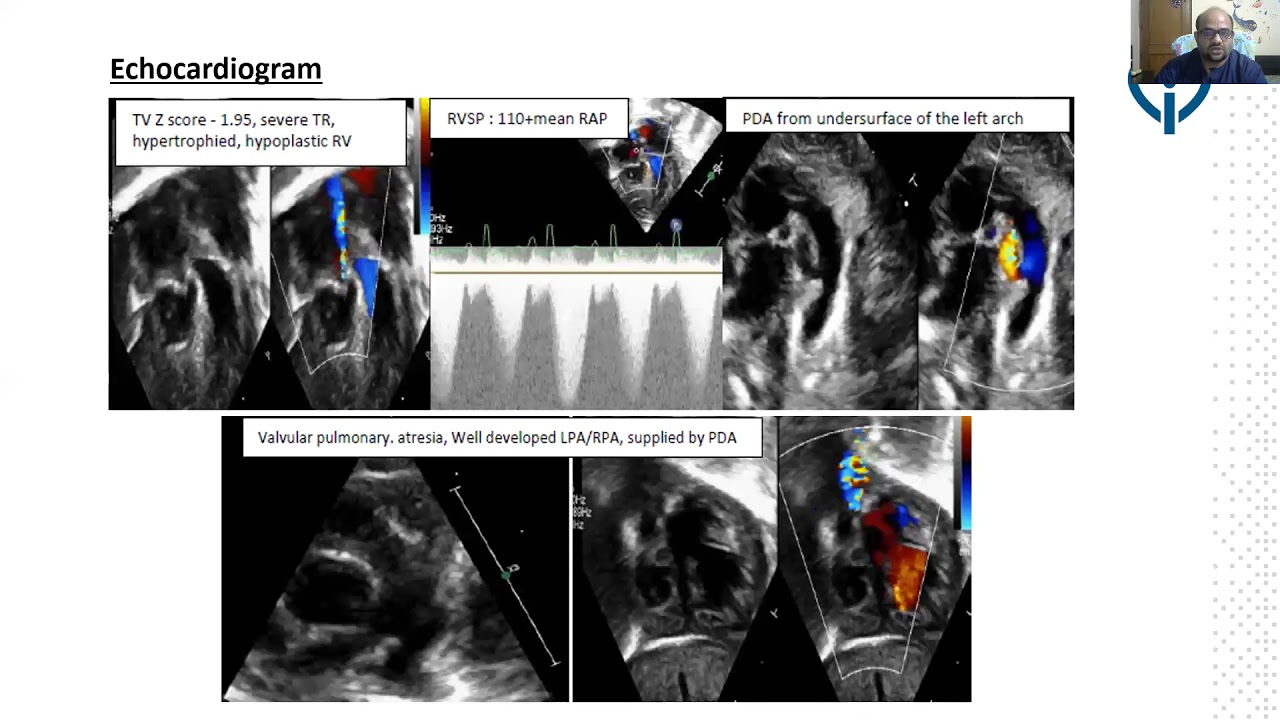

Is there a transcatheter solution for hypoplastic right heart syndrome? : pulmonary valve perforation in a neonate with pulmonary atresia, restrictive VSD and a small right ventricle

By: Sanjeev Hanumantacharya Naganur, Chandigarh, India